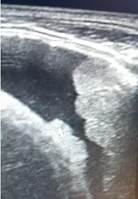

La ecografía torácica (Imagen 4) muestra lesiones de aspecto gelatinoso de bordes irregulares en pleura visceral y parietal de aspecto mamelonado, compatible con infiltración pleural y discreto derrame pleural de aproximadamente 20 ml. Estudio del líquido pleural: Citoquímico normal, inmunohistoquímica negativa, citomorfológico negativo para células malignas.